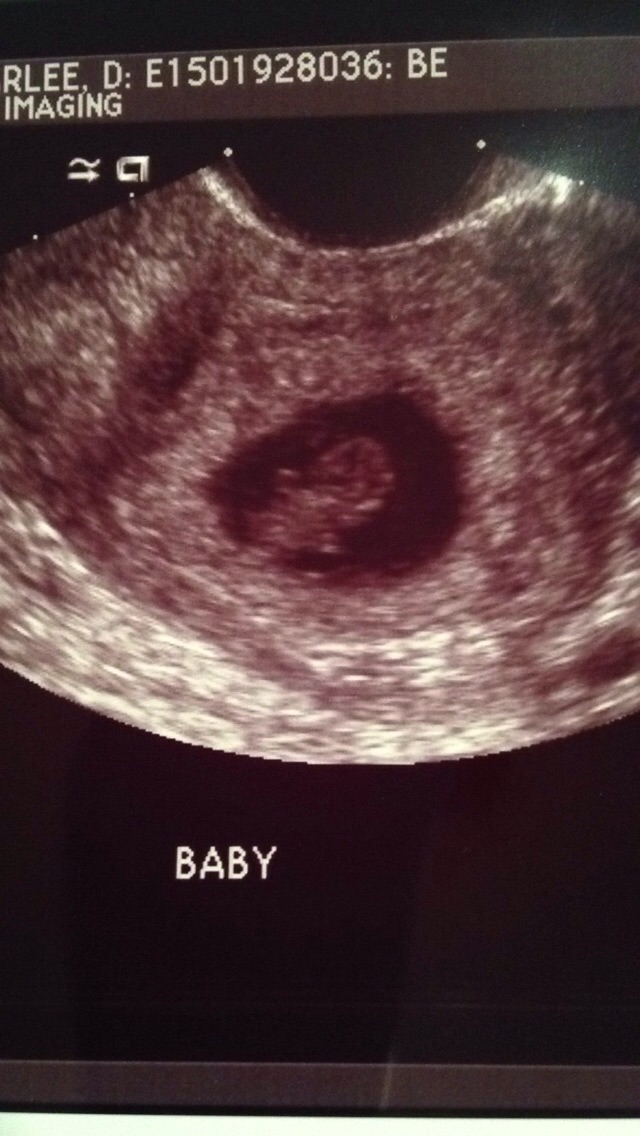

First time mommy. First ultrasound!!

my doctor told me that I was due April 27, but when I had my first ultrasound they measured me at 7w6d putting me at May 5. I haven't seen my doctor since my ultrasound, but the ultrasound tech said that he may keep it at April 27. Anybody else have conflicting due dates? Did your doctor change it?